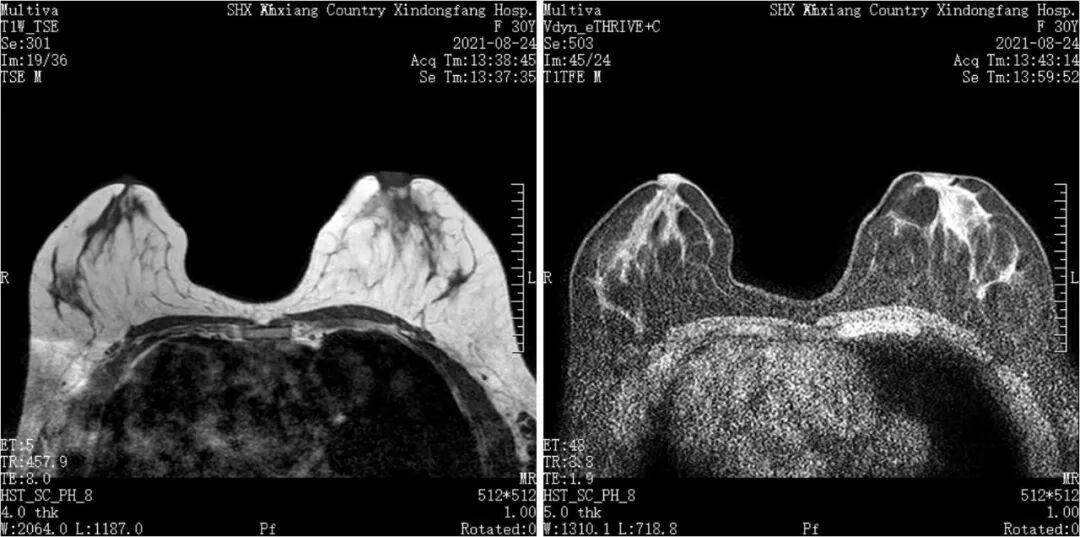

我院飞利浦1.5T磁共振(MRI)具有扫描速度快、成像效果清晰,后处理功能强大等优势,可以满足临床医师和患者的不同需求。磁共振应用广泛,主要用于人体各系统、各部位的肿瘤性病变、感染性病变、代谢性病变、先天畸形以及创伤性疾病的检查,对于神经系统、心血管、骨关节系统、肝脏、脾脏、胰腺、肾脏等腹部脏器以及前列腺、子宫等盆腔实质性脏器的检查独具优势。